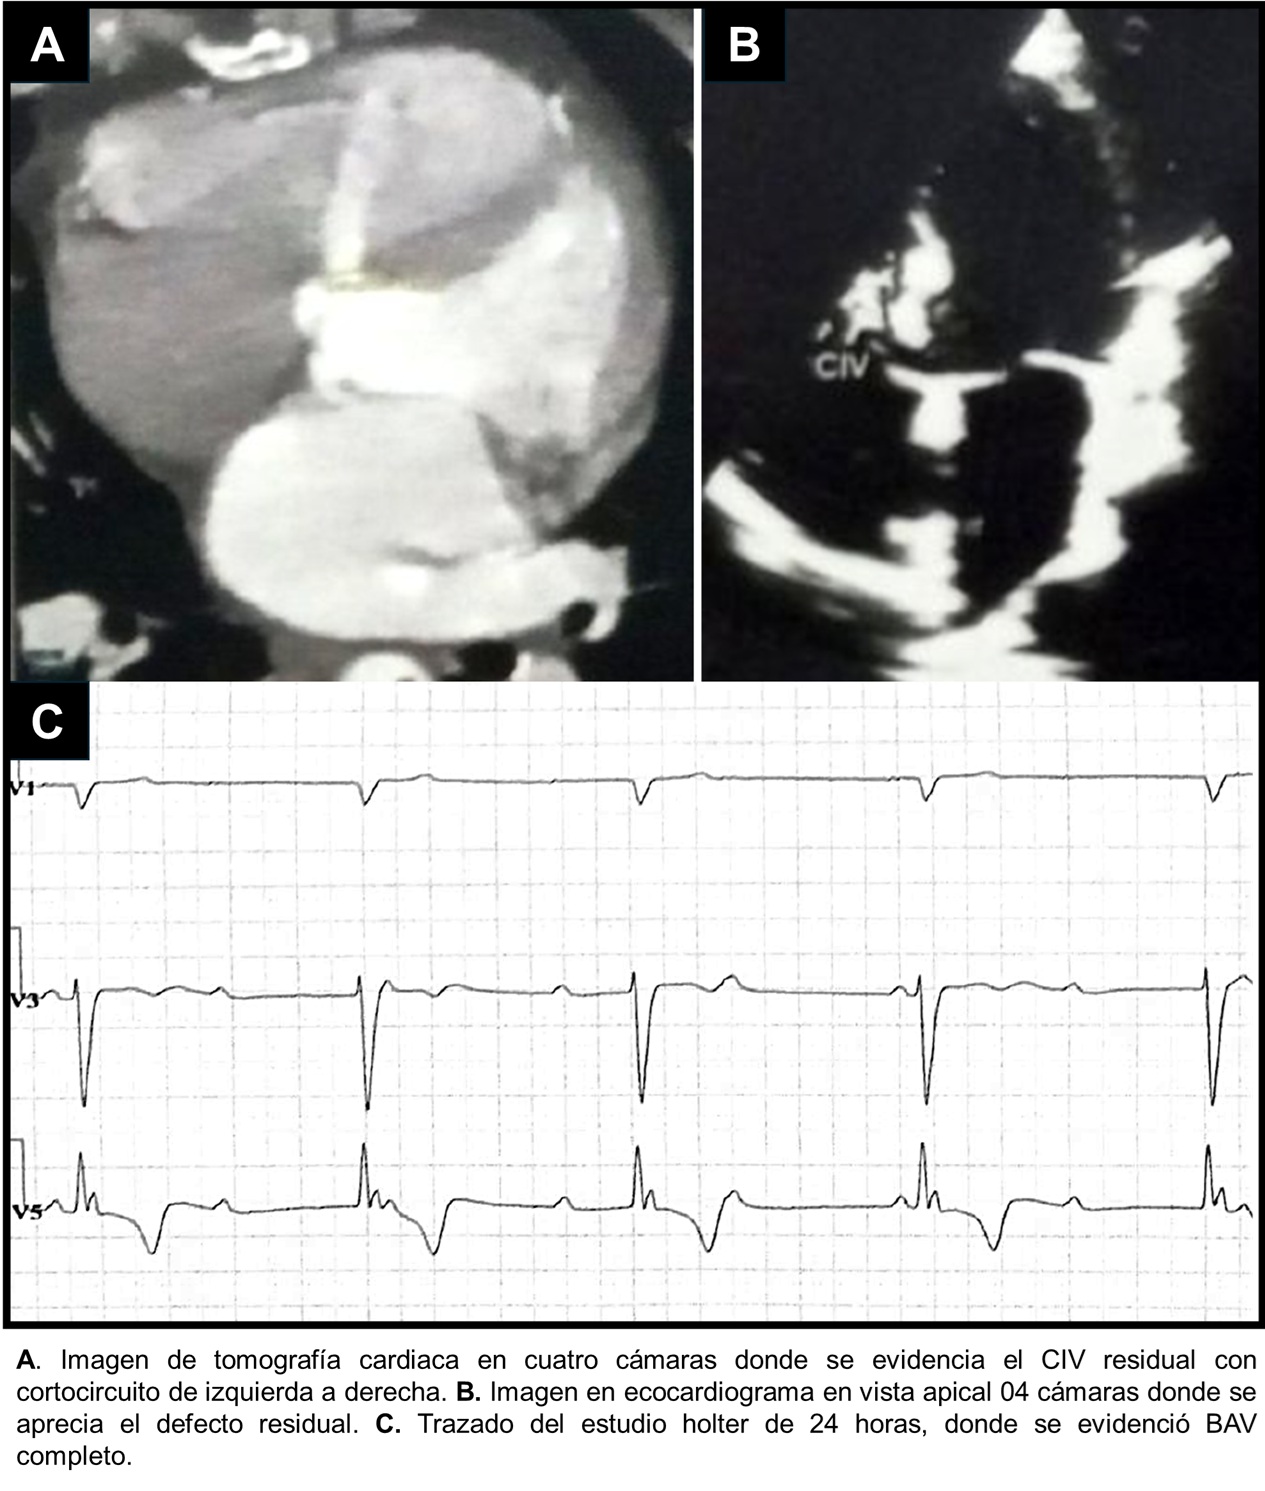

Introducción: El cierre quirúrgico de un CIV peri membranoso, puede traer como...